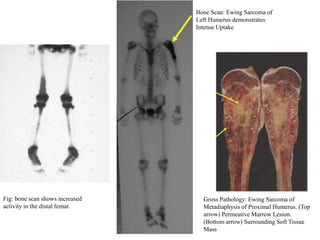

 Bone scan:

◦ To detect polyostotic involvement

◦ to detect bone metastasis

Fig: bone scan shows increased

activity in the distal femur.

Bone Scan: Ewing Sarcoma of

Left Humerus demonstrates

Intense Uptake

Gross Pathology: Ewing Sarcoma of

Metadiaphysis of Proximal Humerus. (Top

arrow) Permeative Marrow Lesion.

(Bottom arrow) Surrounding Soft Tissue

Mass